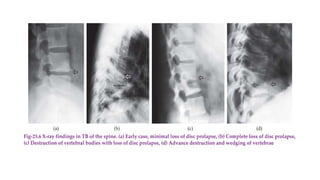

RADIOLOGICAL INVESTIGATIONS

X-ray examination: minimal reduction of disc space in early stage and

may be detectable only on comparing the height of the suspected disc

with those above and below it. In advanced stages, disc space may be

completely lost

• Destruction of the vertebral body

• Evidence of cold abscess